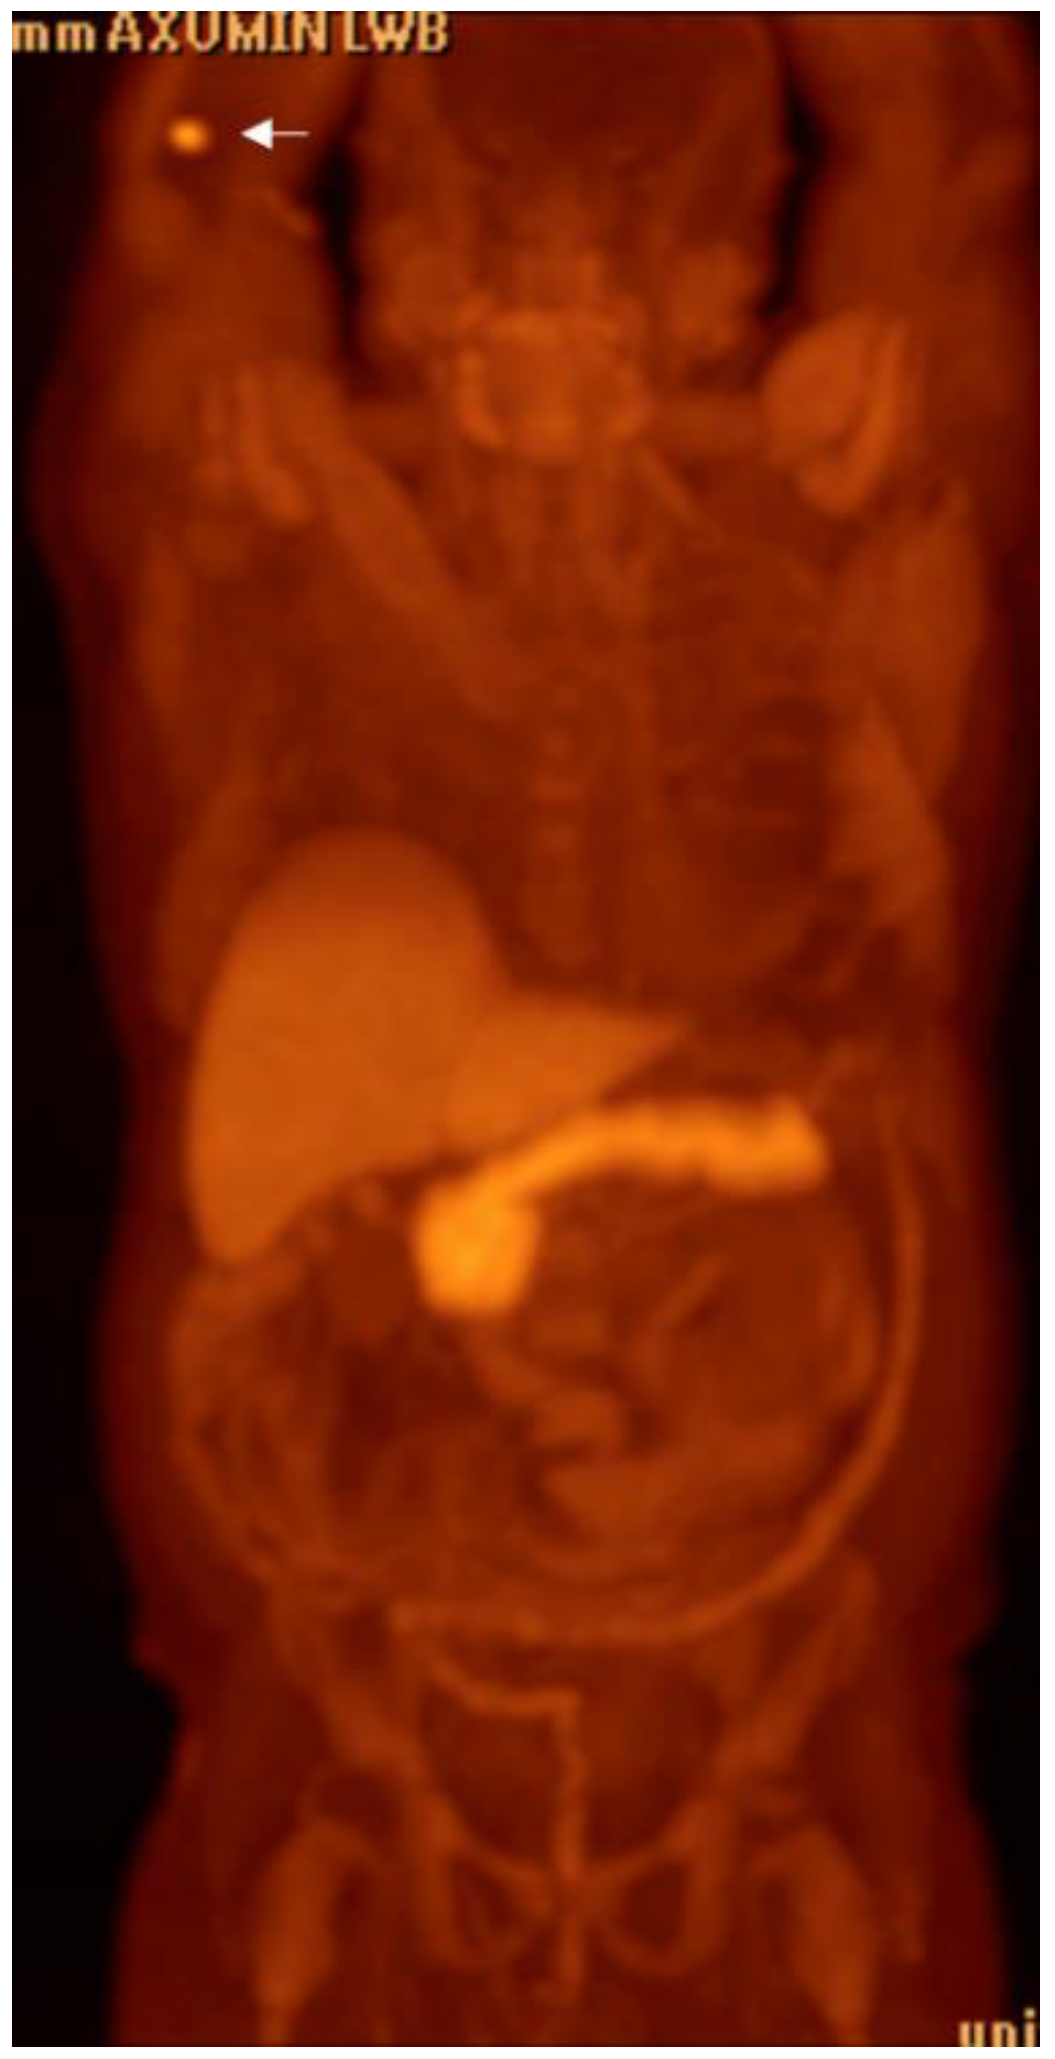

1.9.1. Axumin PET:

Detection of Loco-Regional Disease and Distant Metastases

- Songmen, S.; Nepal, P.; Olsavsky, T.; Sapire, J. Axumin Positron Emission Tomography: Novel Agent for Prostate Cancer Biochemical Recurrence. J. Clin. Imaging Sci. 2019, 9, 49. [Google Scholar] [CrossRef] [PubMed]